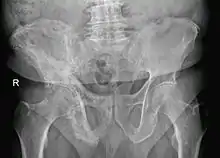

The exact cause is unknown, although leading theories indicate both genetic and acquired factors (see Causes). Paget's disease may affect any one or several bones of the body (most commonly pelvis, tibia, femur, lumbar vertebrae, and skull), but never the entire skeleton,[1][2][3] and does not spread from bone to bone.[4] Rarely, a bone affected by Paget's disease can transform into a malignant bone cancer.

- Pagetic bone has a characteristic appearance on X-rays. A skeletal survey is therefore indicated.

The disease is progressive and slowly worsens with time, although people may remain minimally symptomatic. Treatment is aimed at controlling symptoms, but there is no cure. Any bone or bones can be affected, but Paget's disease occurs most frequently in the spine, skull, pelvis, femur, and lower legs. Osteogenic sarcoma, a form of bone cancer, is a rare complication of Paget's disease occurring in less than one percent of those affected. The development of osteosarcoma may be suggested by the sudden onset or worsening pain.